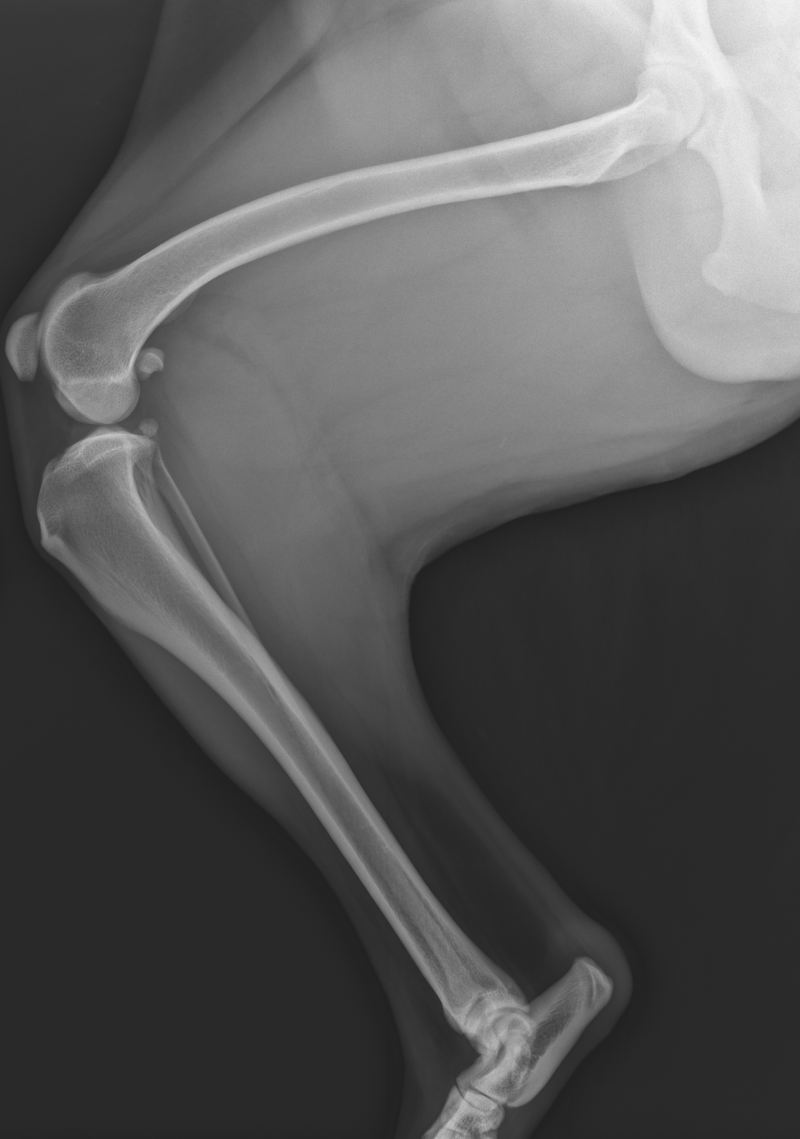

Obrázek 10: Kolenní kloub postižený rupturou LCC, obrázek vlastní

Začínáme s posouzením měkkých tkáních, kde se v případě ruptury vazu objevují i sekundární příznaky, jako například kloubní efúze nebo tvorba osteofytů (11). Tyto příznaky také představují výskyt osteoartritidy. Specifickými známkami chronické ruptury LCC je zbytnění měkkých tkání. V některých případech můžeme pozorovat kalcifikaci zbytků LCC (28).

Snímek posuzujeme i z důvodu, abychom případně odlišili i jiné příčiny kulhání (13). Rentgenologickým vyšetřením můžeme přijít také na patologické procesy, jimiž může být kostní tumor (11).